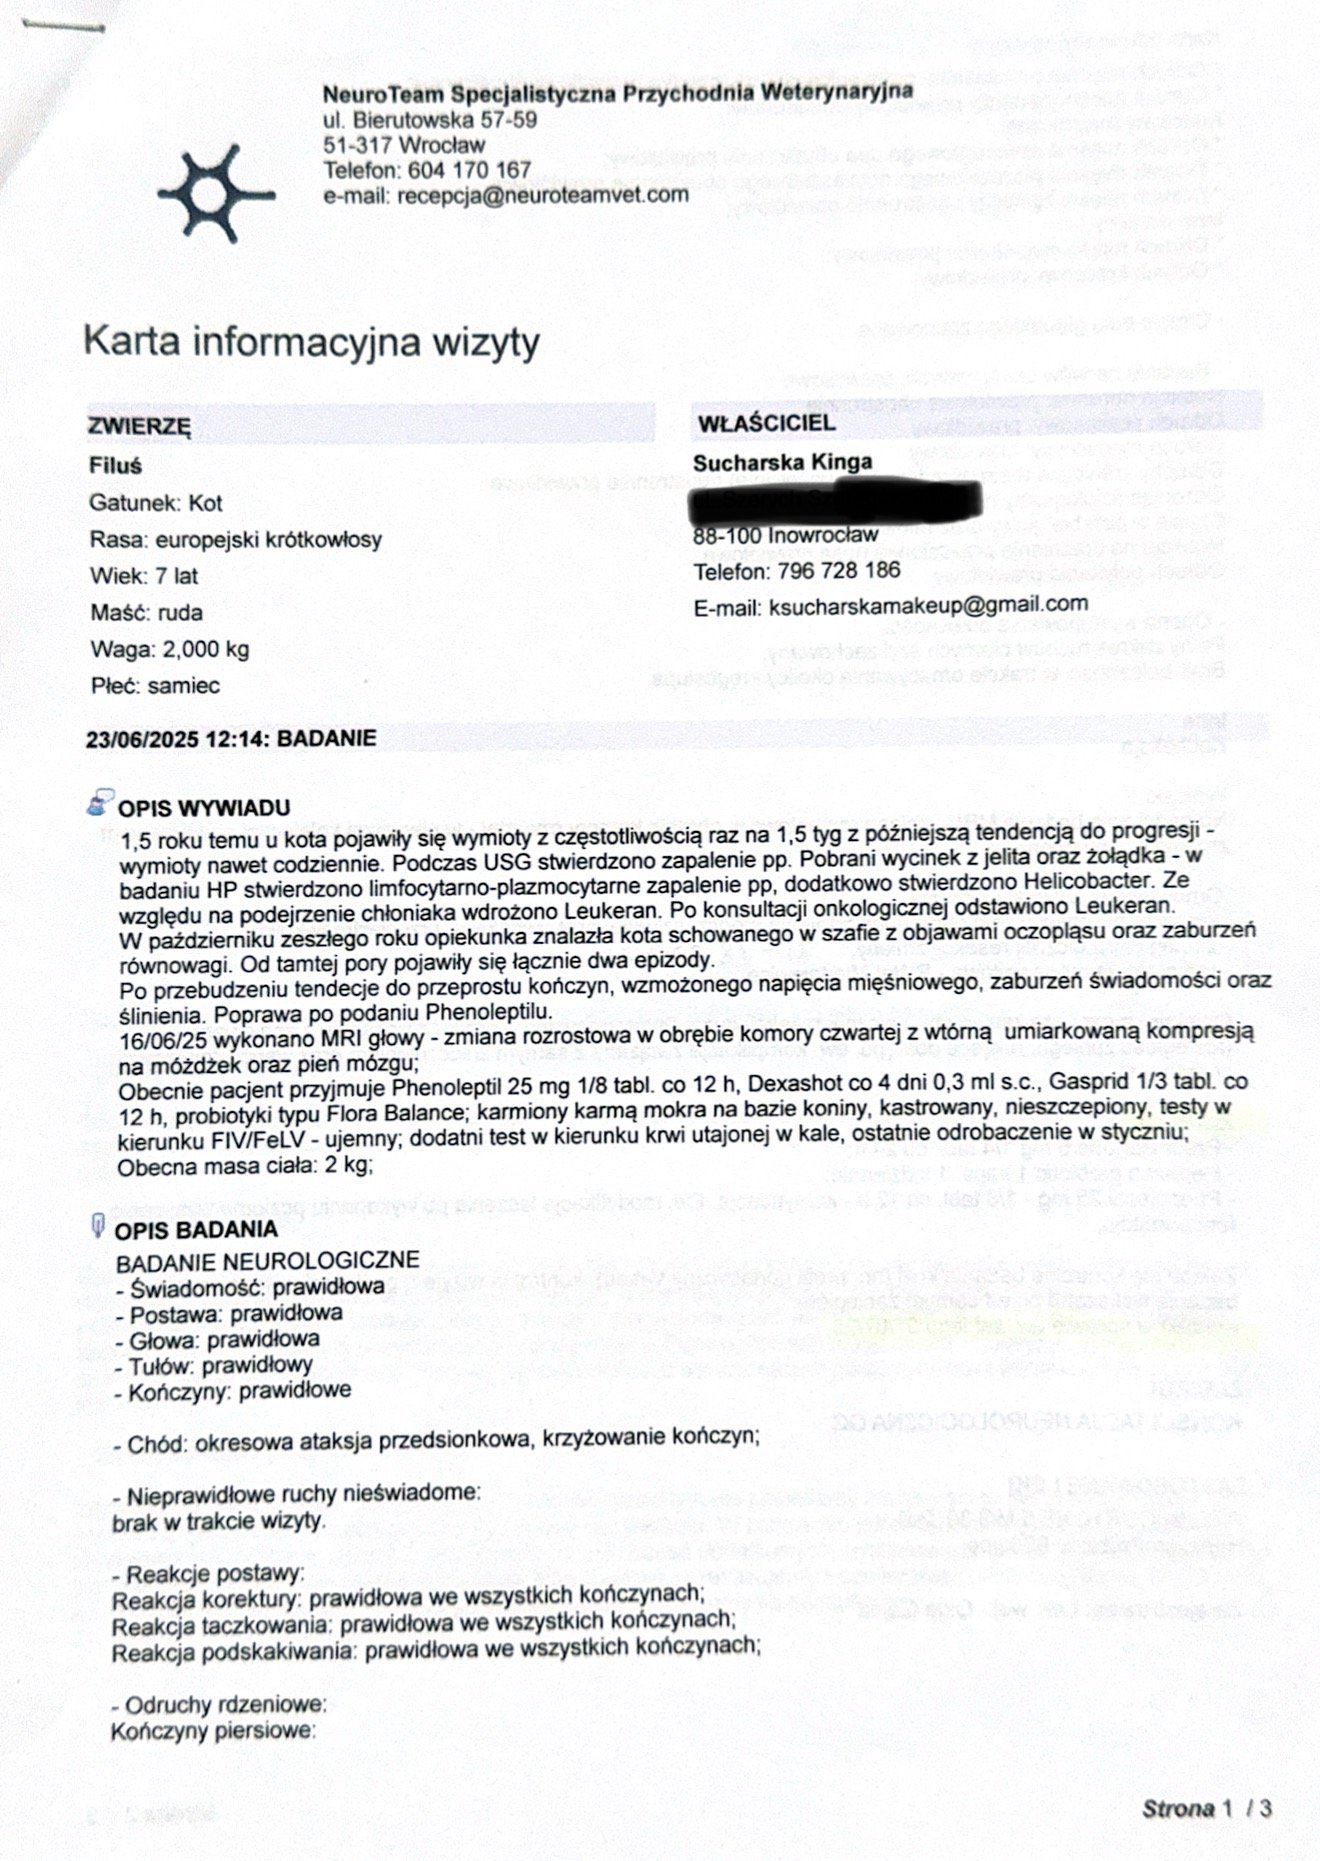

Cześć nazywam się Kinga Sucharska, jestem właścicielką już teraz 2 cudnych kotów. W styczniu 2025 pożegnałam swoją najstarszą kotkę, która zachorowała na nowotwór płaskonabłonkowy żuchwy. Dzisiaj zwracam się do Was z ogromną prośbą w imieniu mojego kotka 7 letniego Filusia o wsparcie finansowe i pomoc w jak najszybszym powrocie do normalnego funkcjonowania i szansy na dalsze życie. Po prawie 2 latach diagnostyki, leczenia w ciemno, czy doraźnej pomocy farmakologicznej otrzymaliśmy diagnozę w postaci nowotworu mózgu jakim jest OPONIAK. Na szczęście dostaliśmy szansę i możliwość na usunięcie guza w klinice NeuroTeam we Wrocławiu. Niestety Koszt takiej operacji wynosi od 15 do 18 tysięcy złotych. Pomijając koszty dalszego leczenia, dojazdów czy ewentualnej dalszej hospitalizacji kotka (cena za dobę w klinice to koszt 900zł). Niestety koszta tejże operacji przerastają Nas, tym bardziej, że jego wcześniejsze diagnozowanie wyniosło mnie już ogromną sumę.

Sierpień 2023 pierwsze pojawienie się wymiotów całą treścią żołądka. Najpierw były rzadziej, a z każdym kolejnym tygodniem zaczęły się zaostrzać. Zaczęliśmy wykonywanie badań u lokalnych przychodni weterynaryjnych takie jak: morfologia, biochemia, b12, t4, USG, rtg - niestety bez żadnych większych nieprawidłowości. Badania te były powtarzane, aż zdecydowaliśmy się szukać pomocy gdzieś dalej. Maj 2024 Przenieśliśmy się do Sweet Vet w Bydgoszczy gdzie później zaproponowano nam gastroskopię z laparotomią oraz dodatkowym badaniem na chłoniaka. Z wycinków histopatologicznych otrzymaliśmy odpowiedź: limfocytarno plazmocytarne zapalenie jelit, helicobacter oraz wynik na chłoniaka: nie stwierdzono ale nie wykluczono… Po zabiegu Filuś źle się czuł więc przez 5 dni jeździliśmy na kroplówki i zastrzyki. Podjęliśmy wstępne leczenie, steryd, probiotyki, przeciwwymiotne, kroplówki. Po braku rezultatów doktor podejrzewała ukrytego chłoniaka dlatego zdecydowaliśmy się podjąć próbę z leukeranem podawanym co 2 tyg. Nadal bez skutku. We wrześniu 2024 Zaczęłam szukać kliniki specjalizującej się w gastroenterologii i tak trafiliśmy do doktor Gójskiej w Labros w Warszawie oraz doktor onkolog Dagmary Księżnej w DobryWet w Bobrowcu, 30minut od kliniki Labros. Dystans, który pokonujemy na wizyty to prawie 300km. U obu doktor z zaleceń podjęliśmy wykonanie szeregu badań od podstawowych, aż po bardziej zaawansowane. Badania, które miał zlecane i wykonywane m.in morfologia, biochemia, t4, badanie kału na strawność, giardia, pasożyty, profile jelitowo trzustkowe, testy symulacji kwasów żółciowych, amoniak z krwi, fiv/felv, koronawirus, badania moczu, przeciwciała p. acetylocholin, dermatofity, elektroforeza białek, SAA, toksoplazmoza, miastenia, RTG, USG, echo serca, kompleksy immunologiczne… Na USG - spowolniona perystaltyka jelit, płyn w przewodach żółciowych.

W październiku 2024 zauważyłam pierwszy dziwny objaw w postaci oczopląsu oraz omdlenia. Zrobiliśmy podstawowe badania tj morfologia, ciśnienie, glukoza, osłuchanie klatki piersiowej - taki zalecono nam krok. Wszystko wyszło w porządku. Objaw ten nie powtórzył się, obraliśmy to jako skutek osłabienia oraz kacheksji.

W Lutym 2025 zdecydowaliśmy się na konsultacje oraz zabieg w KoniczynaWet w Warszawie, aby sprawdzić czy problem czasami nie siedzi w jamie ustnej, oprócz wyrwania 2 zębów i oczyszczenia ich nie stwierdzono żadnych nieprawidłowości oprócz wąskiej szpary w stawach skroniowo żuchwowych. Aby cokolwiek wykluczyć lub stwierdzić zalecono nam tomograf głowy. Z czasem znowu zauważyłam omdlenia u Filusia, które zaczęły pojawiać się częściej. Był to upadek na bok, wraz z prężeniem kończyn oraz ślinotok.

W marcu 2025 wybraliśmy się na wizytę u pobliskiego polecanego neurologa w Aura Łochowo gdzie doktor zalecił nam wykonanie rezonansu z pobraniem płynu mózgowo rdzeniowego oraz wstępnie przepisał leki p.padaczkowe phenoleptil. Z racji wysokiej kwoty zabiegu, a polepszeniu się stanu po lekach trochę uległo to przedłużeniu.

16.06.25 wykonaliśmy rezonans w Poznaniu w klinice Wąsiatycz, który wykazał nam zmianę w postaci oponiaka, niestety bez pobrania płynu ze względu na jego duży nadmiar, a doktor wskazał to jako przeciwwskazanie do wykonania tego zabiegu.

23.06.25 Udaliśmy się z polecenia na wizytę konsultacyjną do kliniki NeuroTeam we Wrocławiu, gdzie dostaliśmy wstępnie zielone światło na wykonanie operacji. Tylko dzięki temu będziemy w stanie uratować mojego Filusia i dać mu szansę na dalsze życie z dala od bólu i cierpienia. Jest ze mną od miesięcznego malucha i nie wyobrażam sobie, aby choroba taka jak ta mi go zabrała, jest moim synkiem. Rokowania bez operacji są bardzo niskie, ze względu na jego dotychczasowe samopoczucie, utrzymujące się wymioty (rzadziej ale jednak nadal występują - w postaci samej wody lub śliny), wagę (2kg) oraz jelita, które słabo pracują pomimo codziennych leków.

Aktualne leki, które otrzymuje to steryd prednicortone, gasprid, ursopol, phenoleptil, rzadziej przeciwwymiotne oraz stale probiotyk